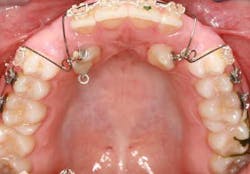

When a full permanent dentition is present (with the exception of impacted canines), the labial/palatal position of the canine will have an influence on what the provider can do. (1) Arguably, obtaining a CBCT is considered mandatory and will allow for a more inclusive treatment plan creation. If angulation is favorable, then consideration to remove the primary canine and wait six months to see if there is movement of the permanent canine is an option. If extraction of the canine(s) is needed, then a premolar substitution, which is dependent on occlusion, can be used in the space. An implant can also be an appropriate alternative. When pulling a canine into the occlusal arch, there is risk involved. Trauma to adjacent teeth (root resorption) and ankylosis are some of the most common complications.The patient was put in full orthodontics and referred to a surgeon for extraction of the primary canines, exposure, and placement of retention on the impacted canines to pull them directly down from their current position.

A ballista appliance was used to prevent a facial pull of the canines in order to avoid and prevent resorption of the roots of the lateral incisors. As movement progressed over the course of the next year, eruption of the canines was considered a success. Once in position, they will be pulled facially into occlusion.

The patient is pleased with the progress reached thus far and is ecstatic at the anticipation of a successful outcome.